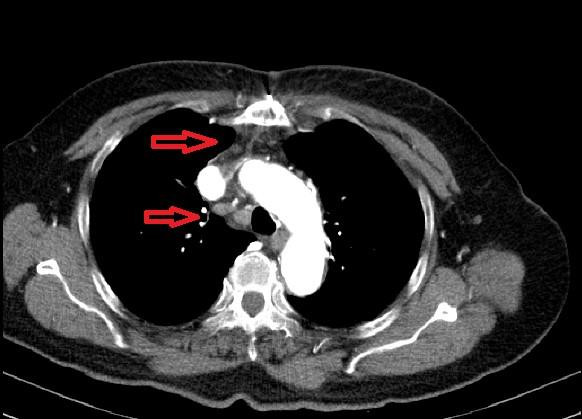

Mặc dù được khám định kỳ và điều trị tăng huyết áp, đái tháo đường theo đơn thuốc ngoại trú. Tuy nhiên, khối u trung thất của bà T. chưa được phát hiện. Các triệu chứng ho khan và mệt của bà chưa rõ rệt. Hơn nữa, với việc chụp Xquang tim phổi thường quy để đánh giá u phổi, u trung thất khó khăn. Cho đến khi mức khó thở, đau đầu tăng lên, kết hợp phim chụp CTcanner cho chẩn đoán xác định khối u lớn trung thất với đặc điểm: Kéo dài từ nền cổ phải xuống trung thất, hình nhiều múi, nằm trước và đè xẹp tĩnh mạch Vô danh. Phần phía trước tĩnh mạch chủ, đẩy lệch và chèn ép khí quản, bao quanh thân động mạch cánh tay đầu, phần ôm quanh tĩnh mạch chủ, tiến ra sau sát cột sống. Quái dị hơn là trong khối rất nhiều tổ chức vôi, xơ mỡ, sợi lông, tóc.

| Phim chụp khối u kỳ quái khổng lồ chứa đầy xơ mỡ, lông, tóc của ngườ phụ nữ Phú Thọ. Ảnh: BS cung cấp |

Bác sĩ Chuyên khoa II Hán Văn Hòa – Phó trưởng Đơn vị Phẫu thuật Tim mạch – Lồng ngực, trực tiếp phẫu thuật cho người bệnh cho biết: “Người bệnh T. được xác định có u lớn dạng u quái trung thất, chèn ép, có chỉ định phẫu thuật. Khó khăn đặt ra là bao xung quanh rất nhiều thành phần quan trọng như: Động mạch chủ ngực, tĩnh mạch chủ trên, thân động mạch cánh tay đầu, khí quản, thực quản, các dây thần kinh, hệ thống bạch huyết....việc lấy toàn bộ khối u tránh tổn thương các thành phần quan trọng xung quanh là khó khăn nhất là khi u rất lớn, 5*6*5 cm, viêm dính, vôi hóa toàn bộ”.